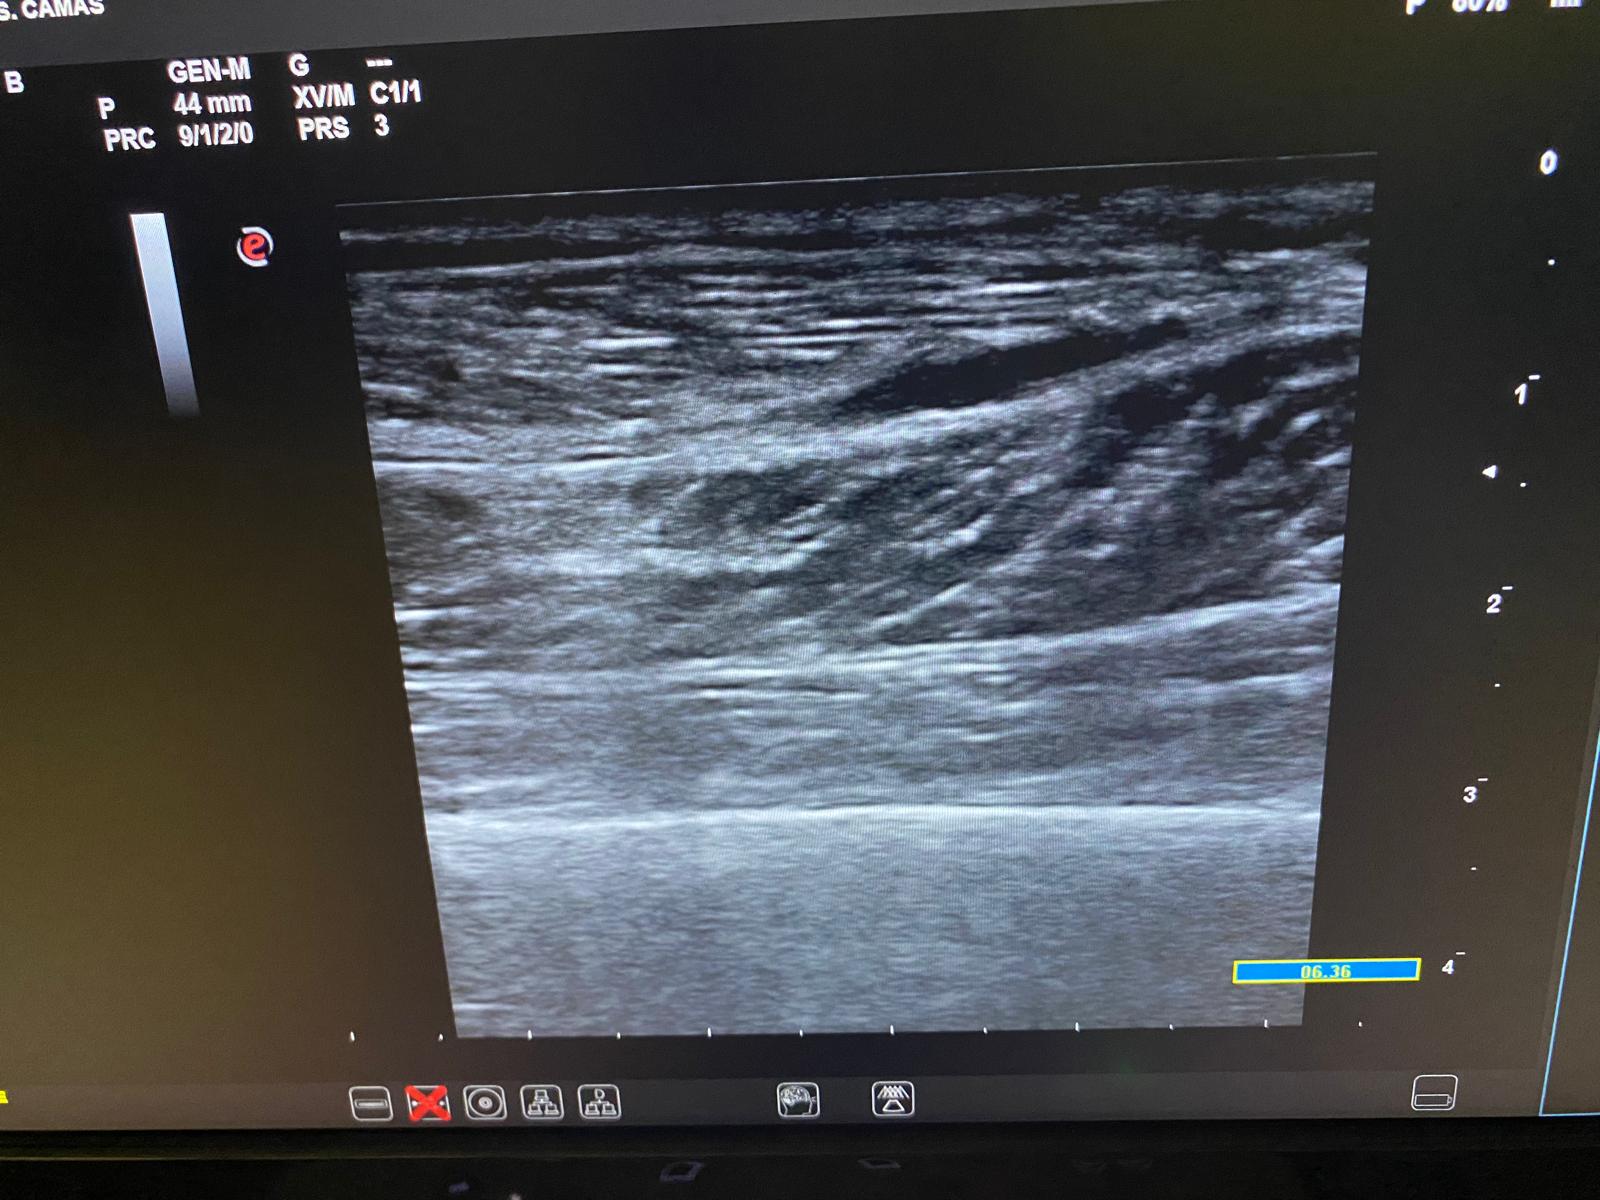

Posteriormente procedemos a la ecografía clínica.

Ecografía clínica en centro de salud: imagen lineal anecoica (compatible con hematoma) entre la aponeurosis del gastrocnemio medial y el sóleo, sin ruptura muscular evidente.

La ecografía clínica nos ha permitido un diagnóstico rápido y preciso, diferenciándolo así de otras patologías con diferente manejo, evitando derivaciones innecesarias y pautando el tratamiento médico de forma precisa y precoz.